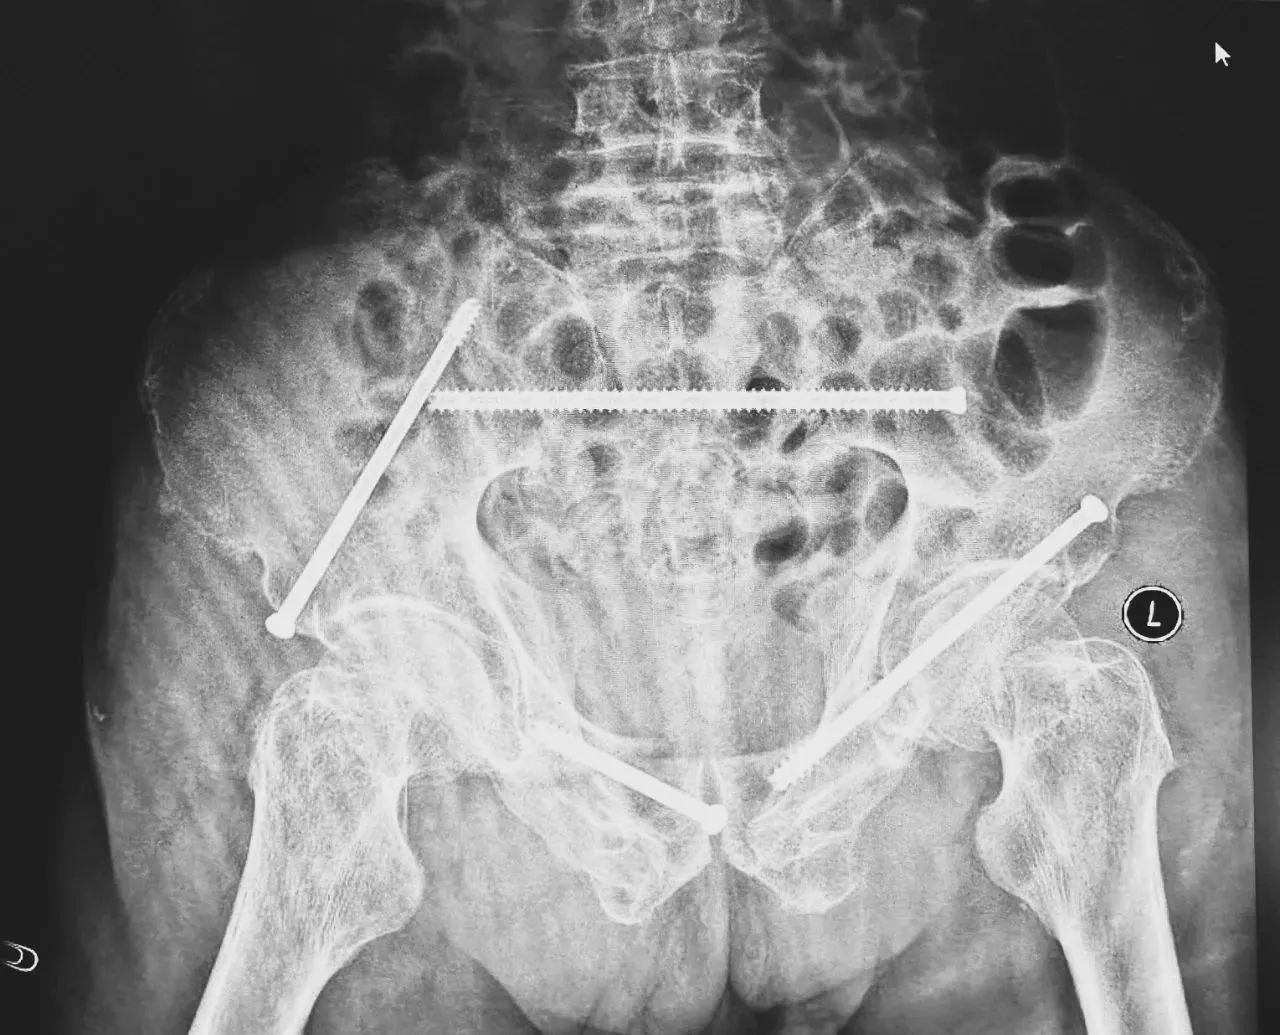

無影燈下,智能骨科團隊將患者示蹤器,放在左側髂前上棘,使用術中三維影像設備獲取骨盆的三維圖像,掃描結果傳輸至機器人導航系統(tǒng),完成螺釘置入的位置和走形,并在機器人的引導下分別置入4枚通道螺釘。置入后再次進行CT掃描驗證,證實導針精確置入。

在骨科手術機器人毫米級精度的引導下,這項原本高難度、高風險的手術變得更加精準高效。手術共計耗時1個半小時,術中出血不到20毫升,每枚螺釘置入位置的切口長度約1.5厘米,完美達到了預期。術后,王大爺安全返回病房。

術后第二天,醫(yī)生團隊復查X片顯示螺釘植入位置非常滿意,骨折基本達到穩(wěn)定復位,同時,復查的全血細胞計數(shù)中,血紅蛋白指數(shù)為102g/L。術后第三天,在智能骨科病房護理團隊及康復師的指導和護理下,王大爺可以坐立在床上。術后第四天,王大爺迎來了出院日,“得虧有了這么先進的醫(yī)療技術,讓我還能下地行走,謝謝你們!”

螺釘植入位置非常滿意